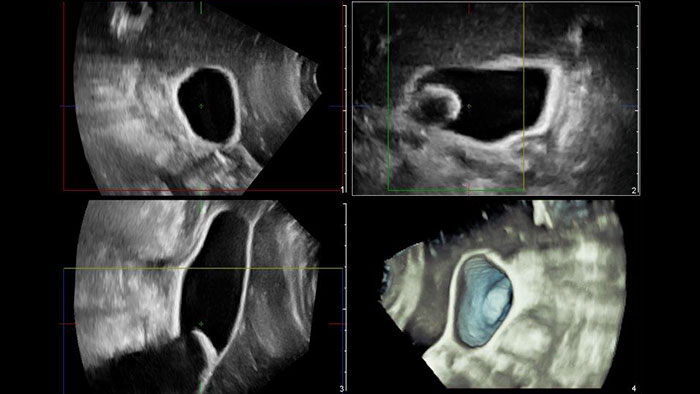

US Q-App General Imaging 3D Quantification (GI3DQ)

Perform advanced visualization and quantification of ultrasound volume

US Q-App General Imaging 3D Quantification (GI3DQ) provides advanced viewing, manipulation, and quantification of 3D data sets. Perform advanced functions such as MPR interrogation, iSlice tomographic imaging, and volume rendering as well as volumetric measurements using multiple methods including semi-automated tools. Results generated from this tool can be appended to the patient’s exam for complete documentation.

Benefits

- Advanced viewing, manipulation, and analysis of 3D ultrasound data.

- Perform multi-planar reconstruction, iSlice tomographic imaging, and advanced rendering functions.

- Easily generate 2D and volume measurements using semi- automated analysis tools.

- Compatible with 3D datasets from Philips EPIQ, Affiniti, iU22, HD15, HD11 and HD9 systems.